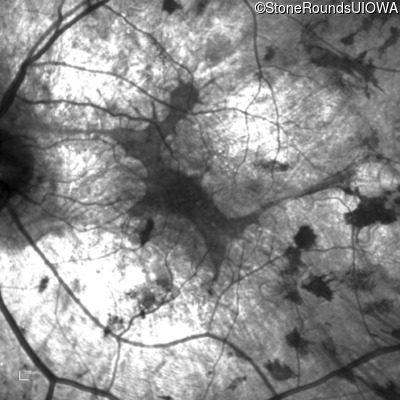

Age at visit: 35 years

This 35-year-old man has trouble in low light and when moving around in busy places. He first reported trouble seeing in low light at age 13. His maternal grandfather was similarly affected.

Age at visit: 37 years